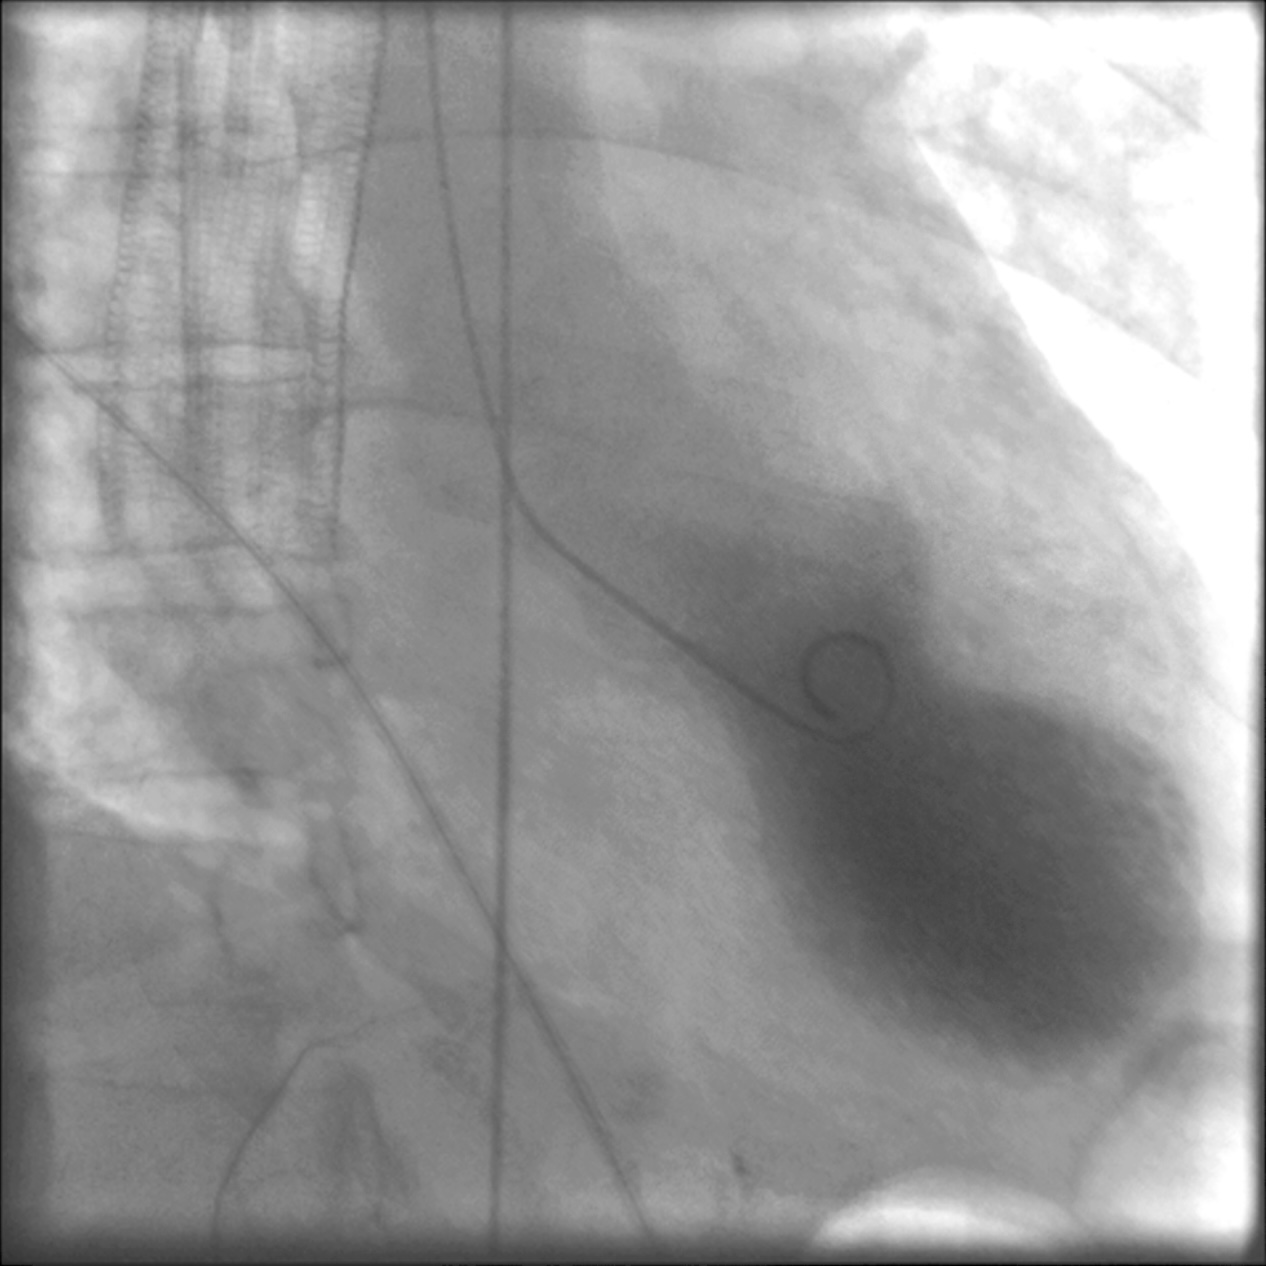

Coronary angiography showing a severe proximal LAD stenosis

Coronary angiography showing severe stenosis of the left anterior descending (LAD) artery

Image: “Coronary angiography showing a severe proximal LAD stenosis” by V. Parisi et al. License: CC BY 2.0